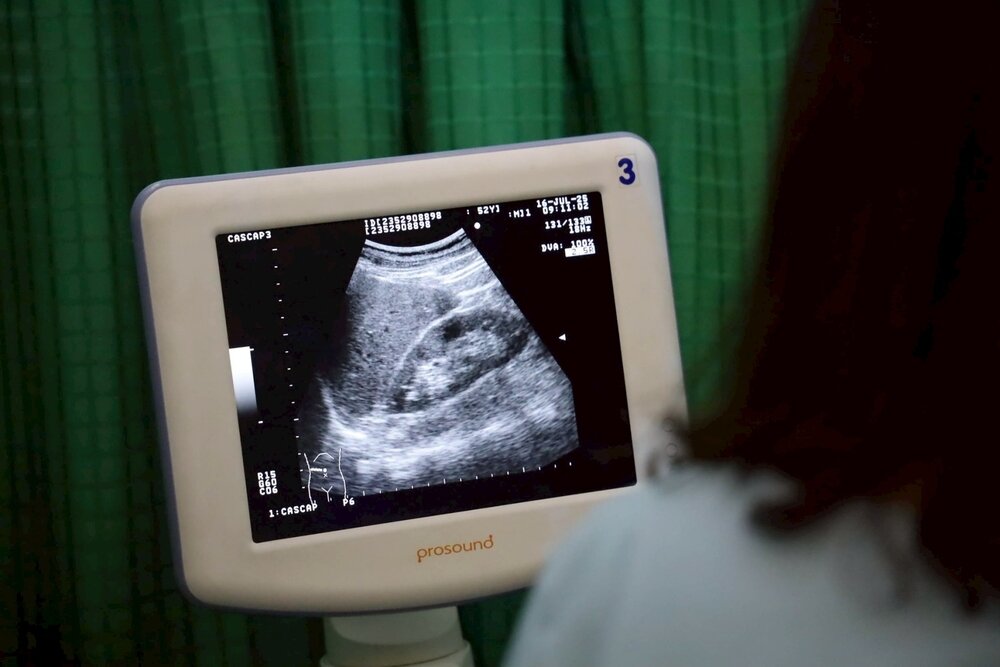

นพ.ศุภกิจ ศิริลักษณ์ ผู้อำนวยการสถาบันวิจัยระบบสาธารณสุข กล่าวว่า การสนับสนุนงบประมาณวิจัยภายใต้งบประมาณของกองทุนส่งเสริมวิทยาศาสตร์ วิจัยและนวัตกรรม (ววน.) เน้นการสนับสนุนทุนวิจัยแบบมุ่งเป้า โดยหยิบยกประเด็นที่เป็นปัญหาสำคัญของประเทศ และมีแนวโน้มที่จะแก้ไขได้มาเร่งดำเนินการ ซึ่งถึงเวลาแล้วที่ทุกภาคส่วนต้องมาร่วมมือกันในการแก้ปัญหาโรคพยาธิใบไม้ตับและมะเร็งท่อน้ำดีให้เกิดเป็นรูปธรรมที่ชัดเจน โดยจุดคานงัดสำคัญของปัญหาดังกล่าวคือพฤติกรรมการบริโภคและการคัดกรองกลุ่มเสี่ยงให้เข้ารับการรักษาได้อย่างรวดเร็ว ทั้งนี้ สวรส. ในฐานะที่เป็นหน่วยงานบริหารและจัดการทุนวิจัย (Program Management Unit: PMU) หลัก ในการขับเคลื่อนเพื่อให้ประเทศไทยปลอดโรคพยาธิใบไม้ตับและลดอัตราการเสียชีวิตจากมะเร็งท่อน้ำดี ตั้งเป้าหมายการขับเคลื่อนเพื่อนำไปสู่การลดความชุกของการเกิดโรคพยาธิใบไม้ตับ ภายใน 2 ปี ให้ได้น้อยกว่า 10% และภายใน 10 ปี น้อยกว่า 1% และสามารถวินิจฉัยโรคมะเร็งท่อน้ำดีได้ตั้งแต่ระยะต้น ภายใน 2 ปี ได้มากกว่า 50% ภายใน 10 ปี ได้มากกว่า 80% โดยจะลดอัตราการเสียชีวิตจากโรคมะเร็งท่อน้ำดี ภายใน 2 ปี ได้มากกว่า 30% ภายใน 10 ปี ได้ 50% สำหรับความร่วมมือกันในครั้งนี้ เราจะช่วยกันผลักดันให้เกิดความปลอดภัย ตั้งแต่เรื่องสุขาภิบาลสิ่งแวดล้อม พฤติกรรมการบริโภคที่ถูกต้อง เพื่อลดการบริโภคปลาดิบที่มีพยาธิใบไม้ตับ การคัดกรองเพื่อให้คนที่มีความเสี่ยงที่จะเป็นโรคมะเร็งท่อน้ำดี สามารถถูกค้นพบได้เร็วขึ้น ไม่ว่าจะเป็นการตรวจอัลตร้าซาวด์ การตรวจ CT Scan การเพิ่มขีดความสามารถในการผ่าตัดให้ได้มากขึ้น ไม่ต้องรอคิวนาน การพัฒนาระบบฐานข้อมูลติดตามและเฝ้าระวังผู้ป่วยโรคพยาธิใบไม้ตับและมะเร็งท่อน้ำดี รวมถึงการขยายการผลิตชุดตรวจคัดกรองให้สามารถเข้าถึงและครอบคลุมกลุ่มเป้าหมายมากขึ้น ซึ่งเราจะทุ่มเทกันทุกภาคส่วน เพื่อดำเนินการให้เห็นผลและบรรลุเป้าหมายที่ตั้งไว้ภายในเวลา 2 ปีต่อจากนี้

รศ.ดร.วัชรินทร์ ลอยลม รักษาการแทนผู้อำนวยการสถาบันวิจัยมะเร็งท่อน้ำดี มหาวิทยาลัยขอนแก่น กล่าวว่า การดำเนินงานตามแผนวิจัยมุ่งเป้าที่เป็นปัญหาสำคัญในพื้นที่และเป็นปัญหาของประเทศด้วยนั้น นับเป็นมิติใหม่ของการดำเนินงานที่จะมีความเข้มข้นมากขึ้น เพื่อยกระดับให้เกิดการแก้ปัญหาที่สามารถเห็นผลได้อย่างชัดเจน ซึ่งมหกรรมตรวจคัดกรองกลุ่มเสี่ยงโรคพยาธิใบไม้ตับและมะเร็งท่อน้ำดี นับเป็นกิจกรรมตามแผนมุ่งเป้า “ประเทศไทยปลอดโรคพยาธิใบไม้ตับ ไม่ตายจากมะเร็งท่อน้ำดี” โดยภายในงานฯ มีการให้บริการตรวจคัดกรองกลุ่มเสี่ยงโรคพยาธิใบไม้ตับ โดยใช้ชุดตรวจปัสสาวะสำเร็จรูปชนิดเร็ว OV ATK ให้กับประชากรกลุ่มเสี่ยงอายุ 15 ปีขึ้นไป จำนวน 2,000 ราย และให้บริการตรวจคัดกรองมะเร็งท่อน้ำดีโดยการตรวจอัลตร้าซาวด์ กับประชากรกลุ่มเสี่ยงอายุ 40 ปีขึ้นไป จำนวน 600 ราย ทั้งนี้กลุ่มเสี่ยงดังกล่าว เป็นกลุ่มที่มีประวัติเสี่ยงข้อใดข้อหนึ่งดังนี้ 1) เคยติดเชื้อพยาธิใบไม้ตับ 2) เคยกินยาถ่ายพยาธิใบไม้ตับ 3) เคยกินปลาน้ำจืดแบบสุกๆ ดิบๆ ซึ่งในงานฯ หากมีการพบการติดเชื้อพยาธิใบไม้ตับหรือตรวจเจอมะเร็งท่อน้ำดี จะมีการแนะนำและส่งผู้ป่วยเข้าสู่การรักษาอย่างเป็นระบบ นอกจากนี้ภายในงานฯ ยังมีนิทรรศการเผยแพร่ความรู้ที่เกี่ยวข้องกับการป้องกันโรคพยาธิใบไม้ตับและมะเร็งท่อน้ำดี อาทิ อาหารปลอดภัย ปลาปลอดพยาธิ หลักสูตรพยาธิใบไม้ในตับและมะเร็งท่อน้ำดีในสถานศึกษา อำเภอต้นแบบ การจัดสุขาภิบาลสิ่งแวดล้อม การนำหมอลำมาเป็นเครื่องมือสร้างความตระหนักรู้เรื่องพยาธิใบไม้ตับและมะเร็งท่อน้ำดี ตลอดจนบูธนิทรรศการของหน่วยงานเครือข่ายที่ร่วมกันขับเคลื่อนเรื่องดังกล่าว